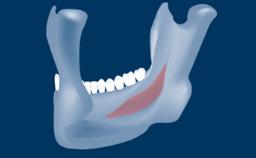

Following tooth loss, alveolar resorption and ongoing pneumatization of the maxillary sinus may lead to vertical and horizontal bone deficits in the posterior maxilla.

This deficit reduces the distance between the maxillary sinus floor and the alveolar process, so that reconstructing the vertical bone height by means of a sinus floor elevation procedure may be a prerequisite for placement of dental implants of the correct dimensions and in the ideal three-dimensional positions in order to achieve optimal functional and esthetic treatment outcomes while respecting relevant anatomical structures.